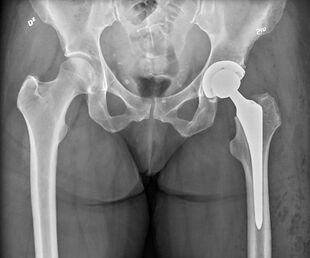

Hemiarthroplasty is a surgical procedure that replaces one half of the joint with an artificial surface and leaves the other part unchanged. This class of procedure is most commonly performed on the hip after an intracapsular fracture of the femur neck (hip fracture). The procedure is performed by removing the head of the femur and replacing it with a metal or composite prosthesis. The most commonly used prosthesis designs are the Austin Moore and Thompson prostheses. A composite of metal and HDPE that forms two interphases (bipolar prosthesis) can be used. The monopolar prosthesis has not been shown to offer any advantage over bipolar designs. The procedure is recommended only for elderly/frail patients, due to their lower life expectancy and activity level. This is because over time the prosthesis tends to loosen or to erode the acetabulum.[84] Independently mobile older adults with hip fractures may benefit from a total hip replacement instead of hemiarthroplasty.[85]

Hip prosthesis for hemiarthroplasty. This example is bipolar, meaning that the head has two separate articulations.

X-ray of the hips, with a right-sided hemiarthroplasty